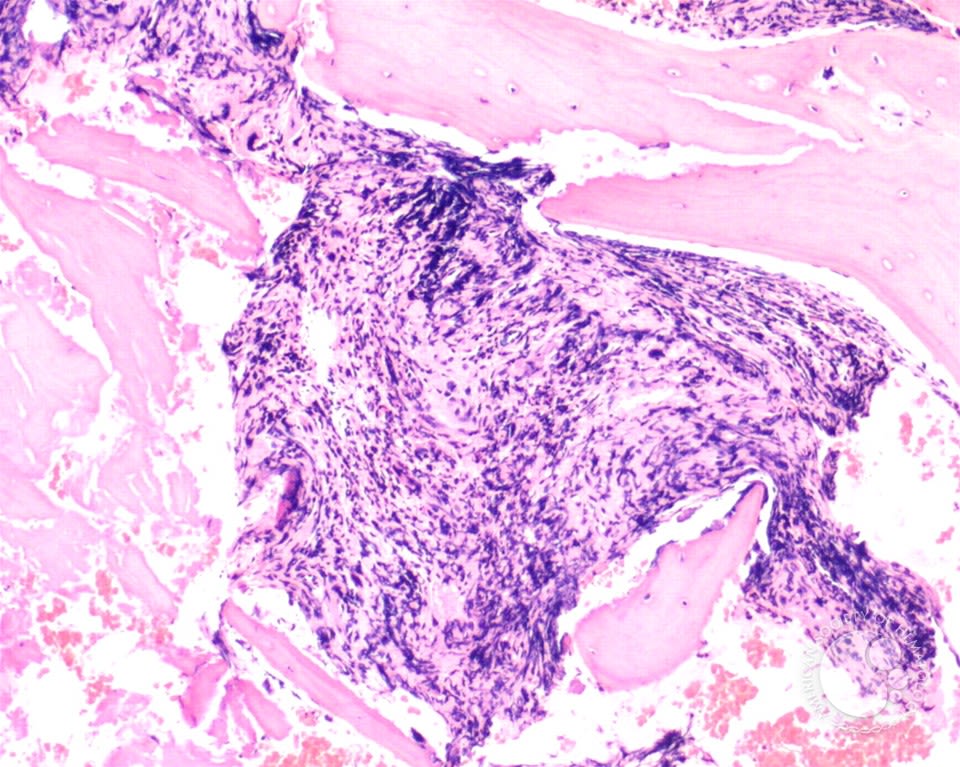

Primary myelofibrosis is a disorder in which the proliferation of platelet producing cells triggers the production of fibrous scar-like material in the bone marrow. Over time, this destroys the normal bone marrow environment, preventing the production of adequate numbers of red cells, white cells and platelets. This results in anaemia, low platelet counts and the production of blood cells in areas outside the bone marrow. The production occurs in organs such as the spleen and liver which become enlarged as a result.

Myelofibrosis is a rare chronic disorder and it can occur at any age but is usually diagnosed later in life, between the ages of 60 and 70 years. Around one third of people with myelofibrosis have been previously diagnosed with polycythaemia (post-polycythaemic myelofibrosis) or essential thrombocythaemia (post-thrombocythaemic myelofibrosis).